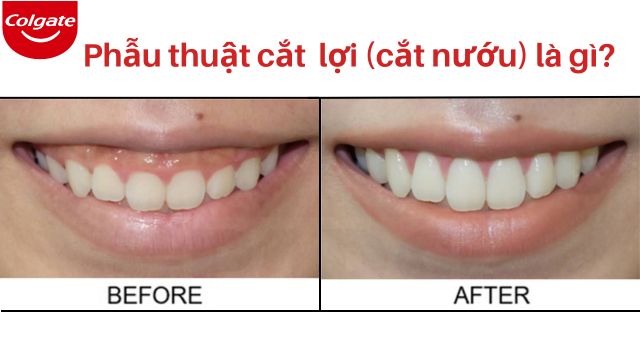

Phẫu thuật cắt nướu: Những Điều Bạn Cần Biết

Phẫu thuật cắt nướu có thể được thực hiện để khắc phục các ảnh hưởng của bệnh nha chu, hoặc để điều chỉnh tình trạng nướu có liên quan đến cấu trúc răng. Tìm hiểu thêm tại đây.

Cắt lợi có đau không? Bao lâu thì lành và những lưu ý khi cắt nướu